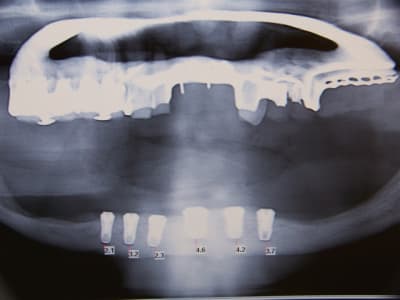

voila un petit cas bien sympa,

cette patiente vient me voir pour poser des implants, elle est edentée complet maxillaire et mandibulaire, et se plaint de l'instabilité de ses deux complets, elle voulait se faire faire ca au portugal mais j ai soigné une amies à elle tres contente du resultat, qui lui conseil de venir me voir, donc avant de partir elle voudrait mon avis.

Et la c'est la surprise, la panoramique parle d'elle meme.

au maxillaire sans greffe d'apposition osseuse je ne vois pas comment faire quelque chose de correct,et à la mandibule à part deux implant symphisaire et locator je sais ps comment faire. J'aurai bien aimé un all on 4 pour eviter de trop appuyer sur les cretes tres resorbées en posterieur avec nerf quasiment sur la crete,

mais meme deux implant la je suis moyen chaud, n y aurait il pas un risque de fracture?